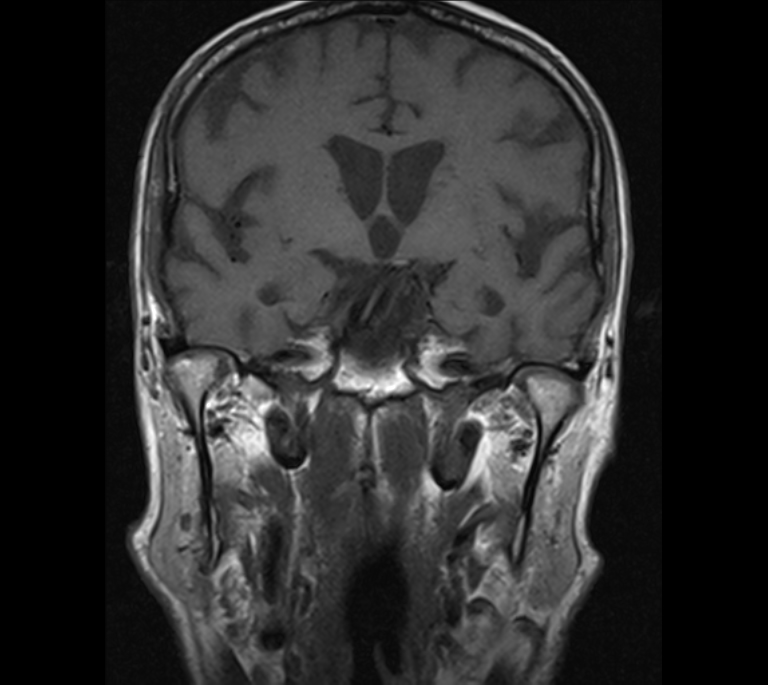

RM Partes Blandas

Prueba diagnóstica no invasiva que consiste en la obtención de imágenes de alta definición anatómica del cuello mediante el empleo de un campo electromagnético y ondas de radio (con un emisor y un receptor). No utiliza radiación ionizante. Indicaciones: sospecha de tumor, infecciones, ganglios.